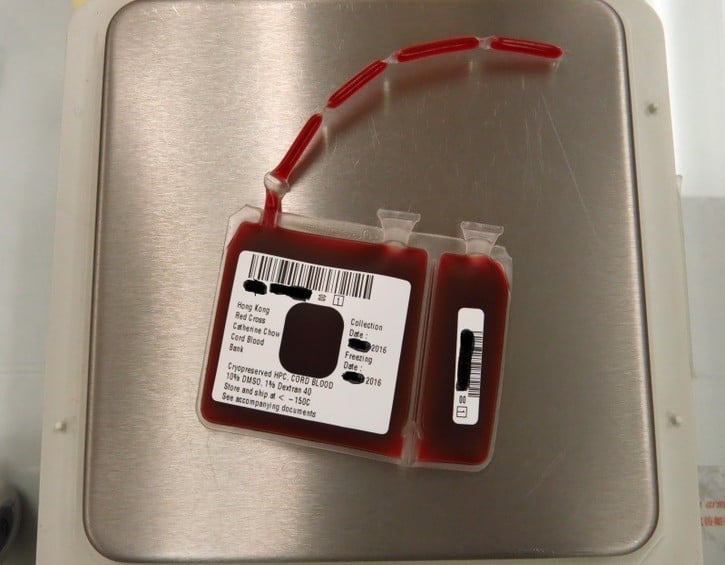

Cord blood must be taken immediately after birth, within 5 to 10 minutes to avoid coagulation, which is why the procedure is only possible if planned before the birth. A needle is inserted at the vein near the end of the umbilical cord after it is cut, with no harm to mum or baby. Blood is then removed from the cord and placenta until it is pale in colour to make sure as much of the blood (and stem cells) is collected as possible. The blood is then placed into a sterile storage bag and is ready to be transported, frozen and stored.

Cord blood banking is done through the Hong Kong Red Cross and can only be performed at two local hospitals – Queen Elizabeth Hospital and the United Christian Hospital. However, if you store through the public sector, there is no guarantee that the blood could be used by you or your child if needed. It can, however, help others in need, so it is the equivalent of donating it to a public blood bank. It is free to have your baby’s cord blood collected and donated to the public bank. That is not an option in the private sector. Additionally, one of the regulations is that the mother cannot have spent more than three cumulative months in the UK between 1 January 1980 and 31 December 1996, which rules out many expat mums. There is also no specific ordinance in regulating the storage of cord blood in Hong Kong, but it does fall under the regulatory control of existing ordinances under different circumstances (similar to that of any organ).

Hong Kong Red Cross Catherine Chow Cord Blood Bank, 15 King’s Park Rise, Yau Ma Tei, Hong Kong, 2710 1333, 2710 1236, [email protected], www5.ha.org.hk